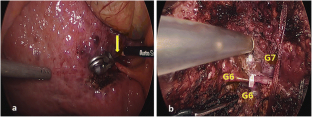

Rouviere’s sulcus is identified after retracting superiorly the gallbladder. The Glissonian approach for anatomical resection of segment VI can be performed with minimal dissection of the liver parenchyma around the sulcus. After clamping the Glissonian pedicle in the sulcus, the ischemic area fed by the portal pedicle was confirmed. The right triangular ligament was divided to create a small opening for placement of the hanging tape along the ischemic line. The liver parenchymal transection was performed along the hanging tape.

Fig. 2

Fig. 3